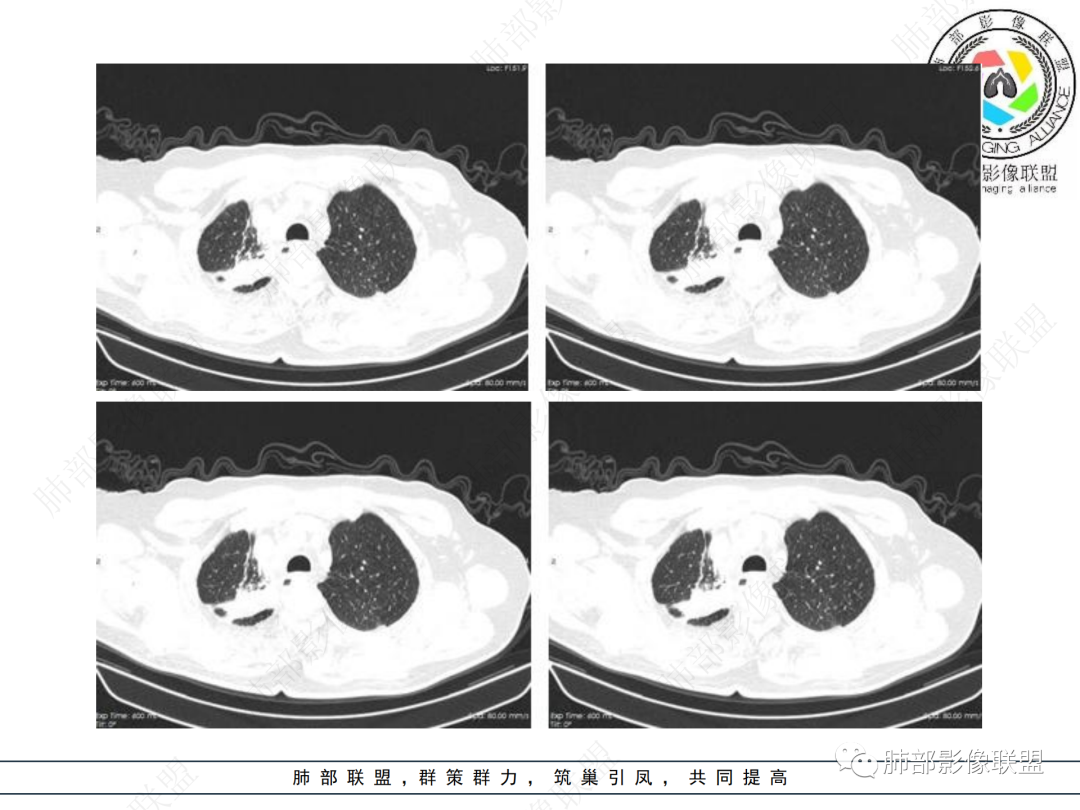

右上胸廓较对侧慢性缩小

右上叶体积缩小

慢性病变有

结合本病例,老年男性患者,慢性病程,急性加重,无吸烟史,影像学表现为右肺上叶尖后段斑片实变密度影,整体边界清晰,边缘平直收缩为主,周边散在纤维条索影,内部见支气管内粘液栓,血管影走形正常,没有明显破坏,增强扫描明显强化,缺乏典型分叶毛刺、胸膜改变,病灶也未显示清楚的磨玻璃勾边,病灶大而肺门纵隔未见肿大淋巴结,综合考虑慢性炎性肉芽肿可能性大。但恶性,结核能完全排除吗?我想对临床医生来说还是有很大考验的。